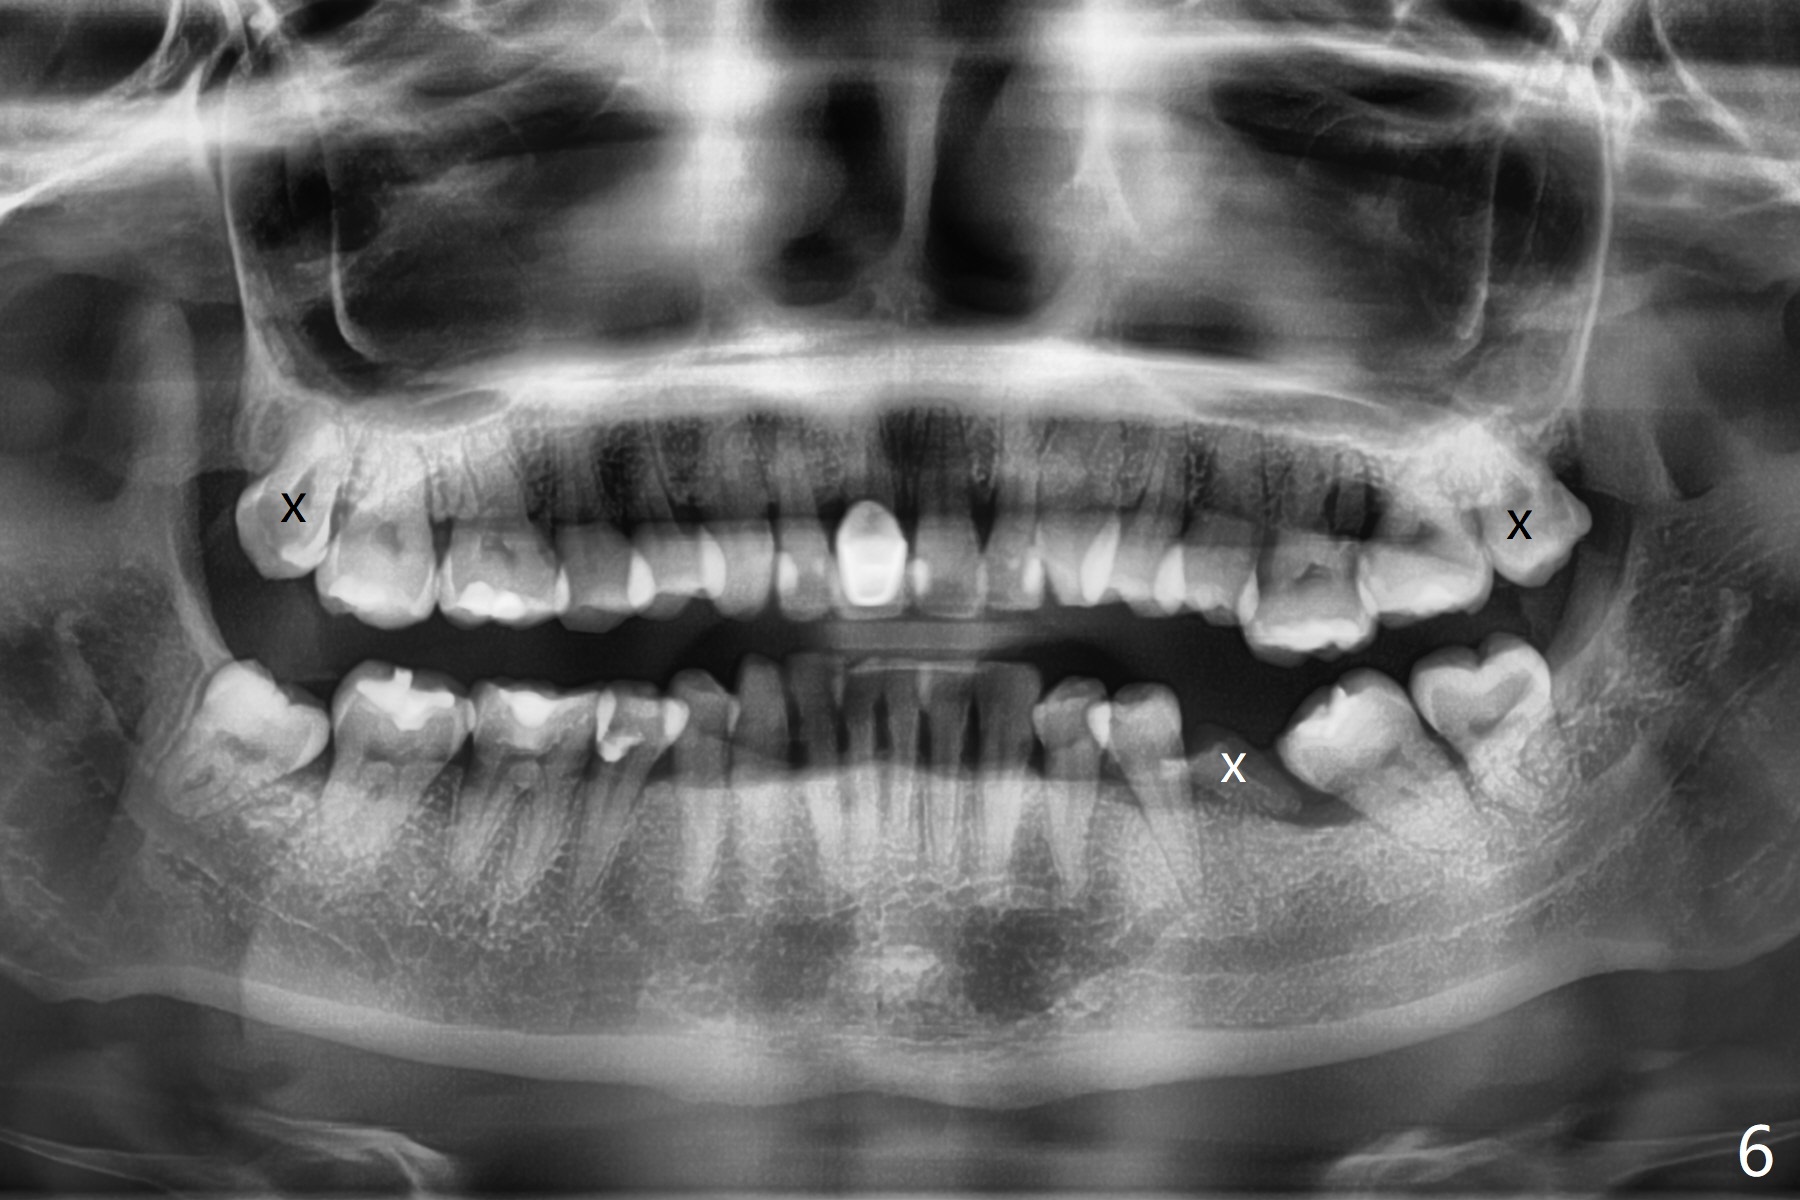

31岁女,牙周炎,安格氏二类错𬌗(图一至八),深洗后,同意牙齿矫正,但是要求保留左下智齿,前移7,8,取代6,左上6过度萌出(图三:箭头)。

初步计划:第一期安置矫正器,排列,建立正常前牙覆合覆盖,二类牵拉。尽量竖直左下7,8(图十一:白色轮廓);使用两个微型植体(图九:黑线(两个植体之间放置power chain(红线)))压入左上6(图十(圆圈:近中微型植体),与图三对比),为左下7近中移位(红色箭头)创造空间。

第二期在左下4和5之间植入微型植体作为支抗(图十一:红色),利用7远中长勾(粉红色)和橡皮筋,先让7平行近中移位,控制根torque。A 31-year-old woman with Class II Division I malocclusion requests orthodontic treatment without extraction of LL8. U8s and LL6 have been extracted with SRP. The 1st stage will be alignment , intrusion of UL6, upright of LL7 and 8 and correction of Class II malocclusion using double twin.